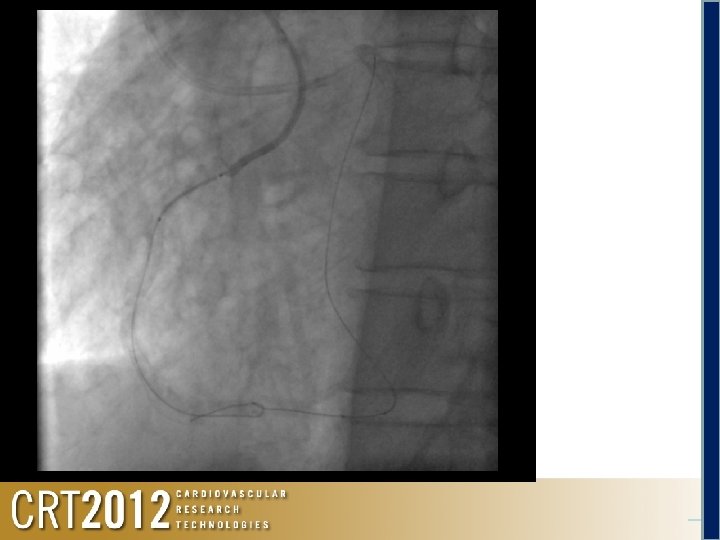

Antegrade Tazuna 1. 25 Retrograde Anchoring at #3 by a Tazuna OTW 3. 0 mm Anchoring

Antegrade Tazuna 2. 5 x 15 Retrograde Anchoring at #3 by a Tazuna OTW 3. 0 mm Anchoring